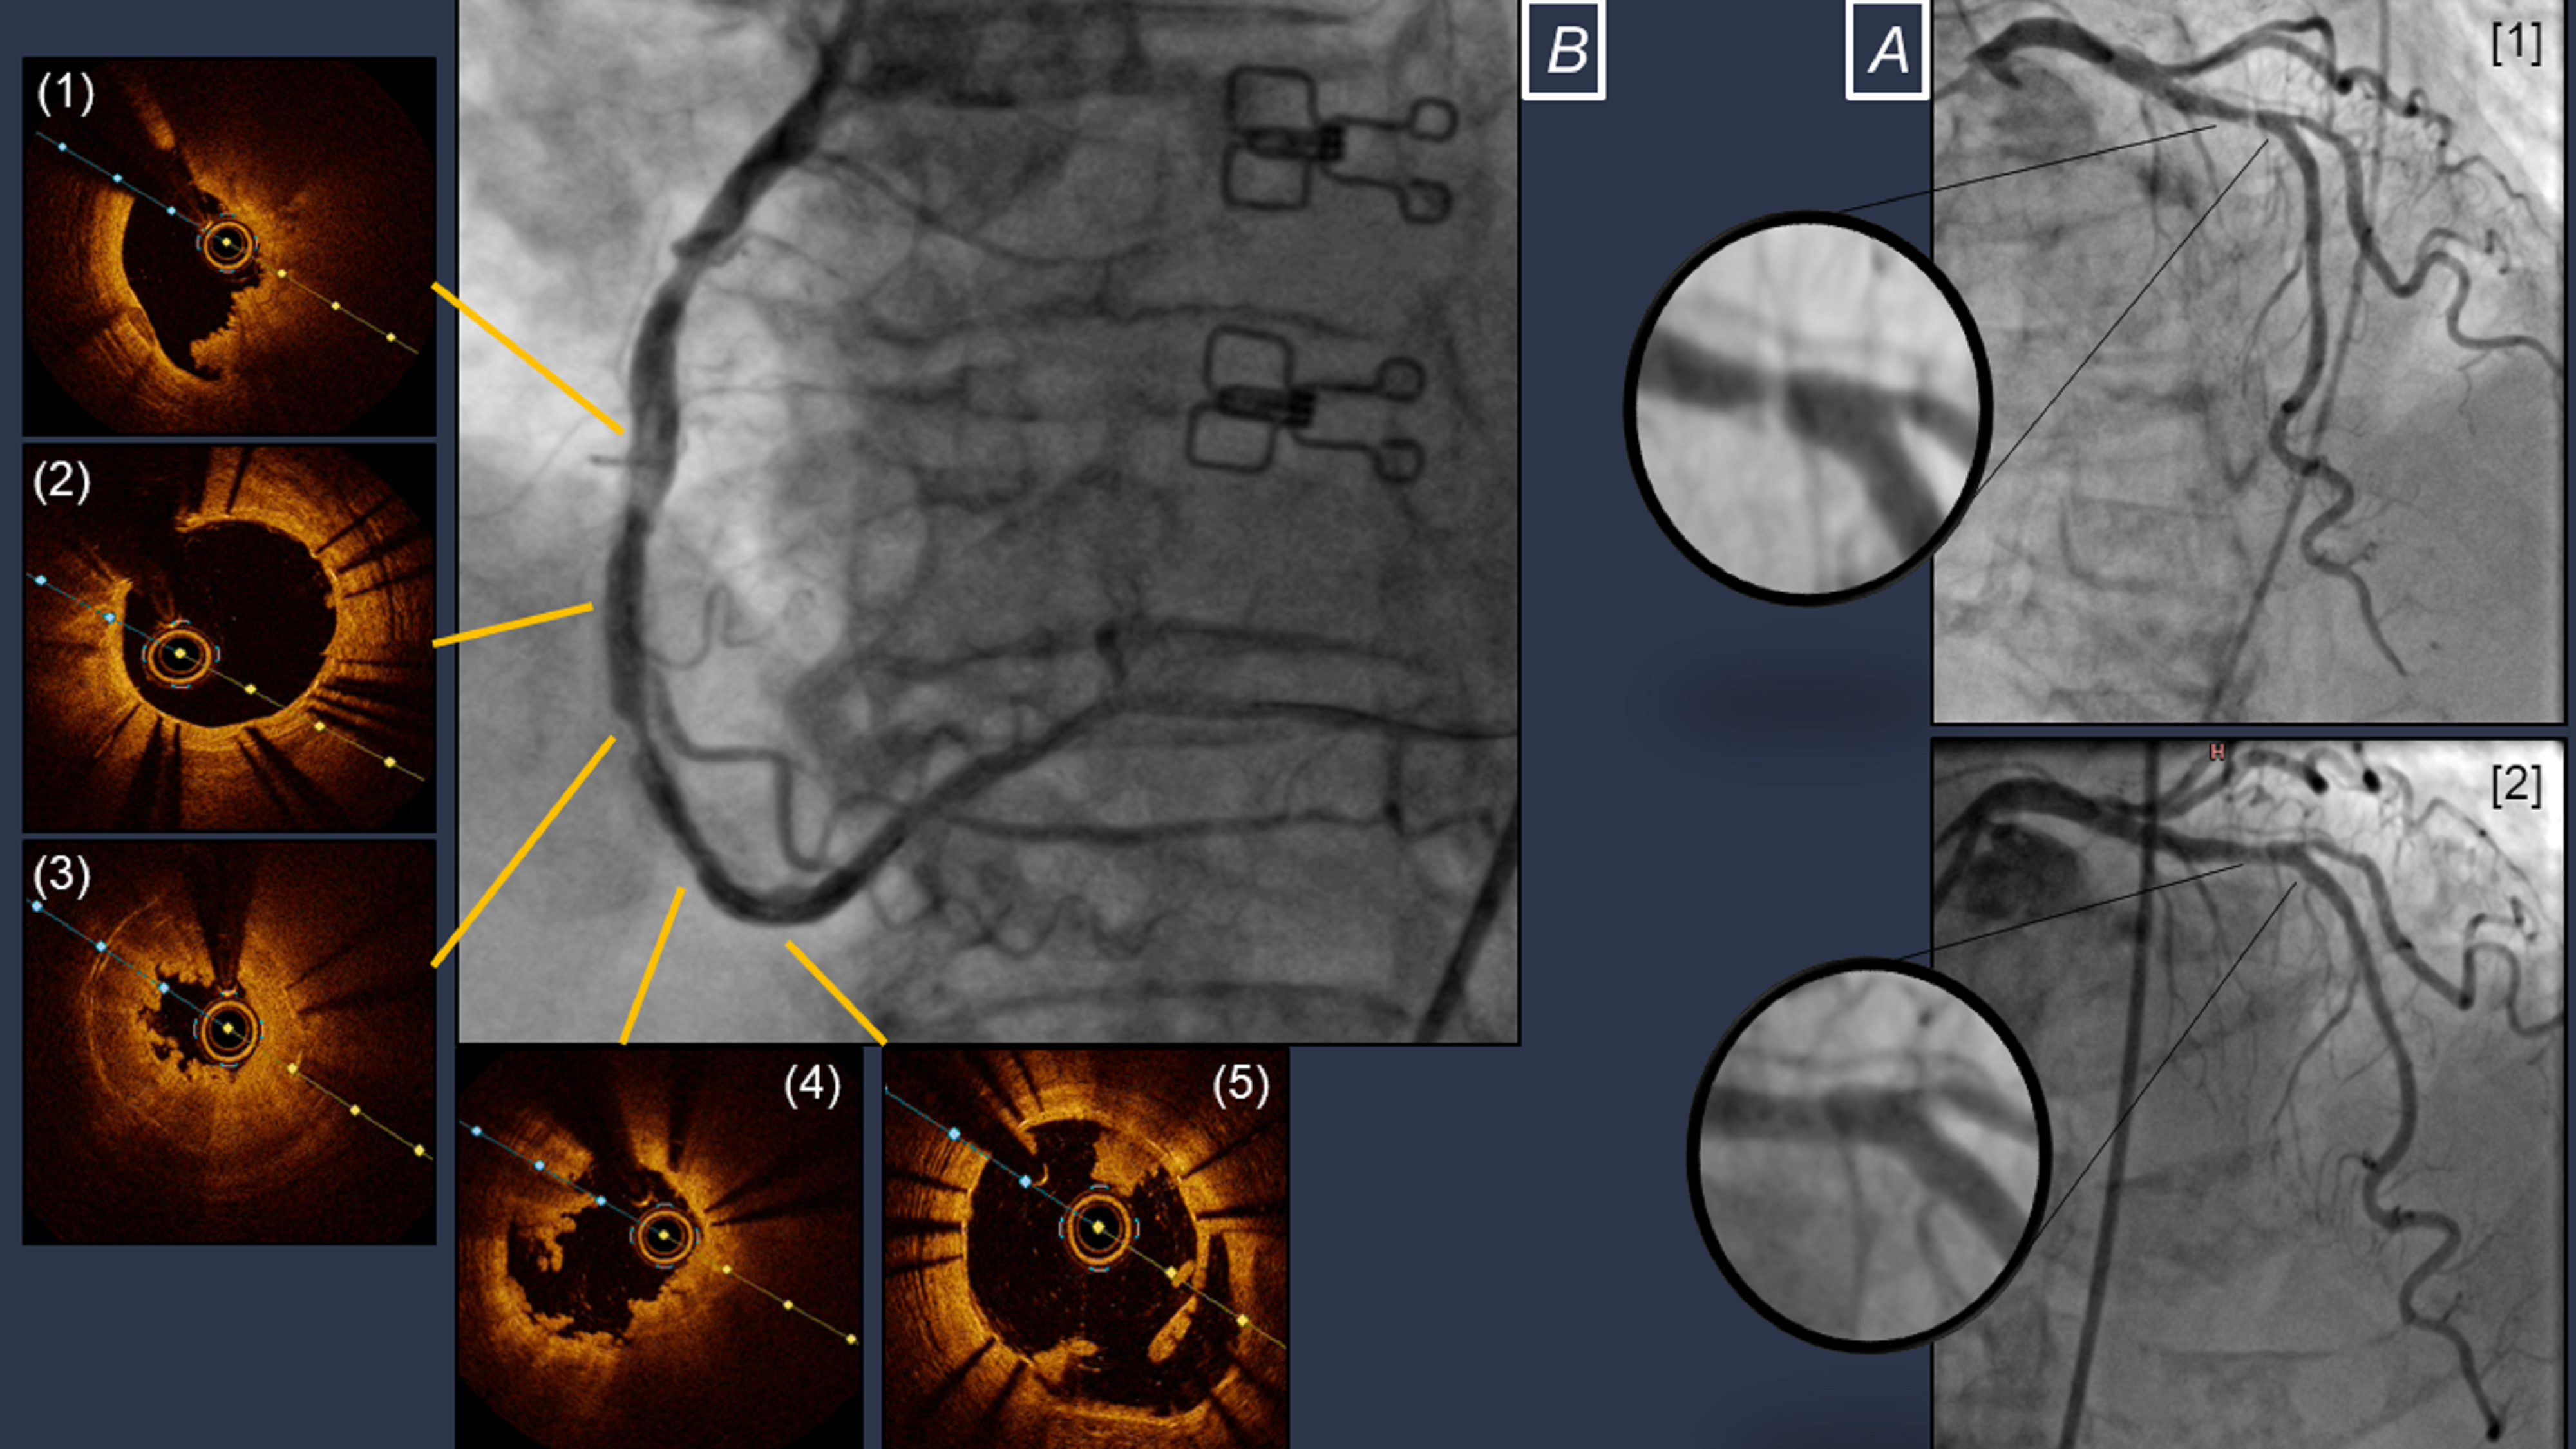

An emergency coronary angiography showed an intraluminal filling defect within the LAD stent, with Thrombolysis in Myocardial Infarction (TIMI)-2 flow (Figure A [1], Video 1), as well as diffuse intraluminal haziness in the RCA with severe in-stent stenosis in the distal segment, while TIMI-3 flow was preserved (Video 2). After wiring the LAD and diagonal branch, the initial filling defect resolved and TIMI-3 flow was re-established, implying a possible peripheral embolization of thrombus fragments following wire manipulation (Figure A [2], Video 3).

Despite restored LAD flow, the patient continued to experience chest pain and ECG abnormalities. The distal RCA stenosis was initially treated with drug-coated-balloons, following pre-dilatation with a noncompliant balloon. Optical coherence tomography showed multiple intraluminal thrombi in both the stented and native segments of the RCA, which were interspersed with a stented segment without any significant lesion (Figure B, Videos 4 and 5).